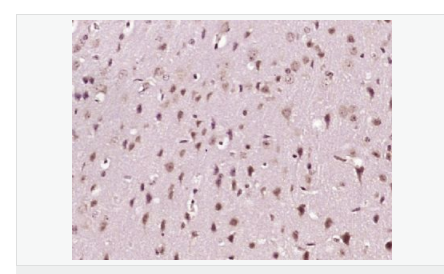

| 產(chǎn)品介紹 | This gene encodes a member of a small calcium-binding EF-hand protein family. The encoded protein is thought to have a key role in Golgi calcium homeostasis and Ca(2+)-regulated signal transduction events. [provided by RefSeq, Jun 2010] Function: Major calcium-binding protein of the Golgi. May have a role in calcium homeostasis. Subcellular Location: Golgi apparatus > cis-Golgi network membrane. Cytoplasm. A small fraction of the protein may be cytoplasmic. Tissue Specificity: Expressed both in fetal and adult heart, lung, liver, kidney and brain, and in adult skeletal muscle, placenta and pancreas. Post-translational modifications: Phosphorylated upon DNA damage, probably by ATM or ATR. Similarity: Belongs to the nucleobindin family. Contains 2 EF-hand domains. SWISS: Q02818 Gene ID: 4924 Database links: Entrez Gene: 4924 Human Entrez Gene: 18220 Mouse Omim: 601323 Human SwissProt: Q02818 Human SwissProt: Q02819 Mouse Unigene: 631602 Human Unigene: 258923 Mouse Unigene: 1492 Rat Important Note: This product as supplied is intended for research use only, not for use in human, therapeutic or diagnostic applications. |